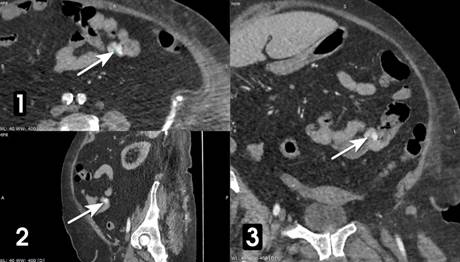

Утром 12 декабря больной выполнена КТ с внутривенным контрастированием (рингоскан 350–100,0 мл). В стенке проксимальной части тощей кишки визуализируется гиперваскуляризированное образование 10 х 12 мм с экстравазацией рентгенконтрастного вещества (РКВ) в просвет кишки (рис. 1, 2).

Рис. 1. КТ органов брюшной полости с внутривенным контрастированием больной Б. В начальном отделе тощей кишки обнаружено гиперваскуляризированное образование (стрелка); (1) аксиальная плоскость; реконструкция в сагиттальной (2) и фронтальной (3) плоскостях. Примечание: составлено авторами по результатам данного исследования